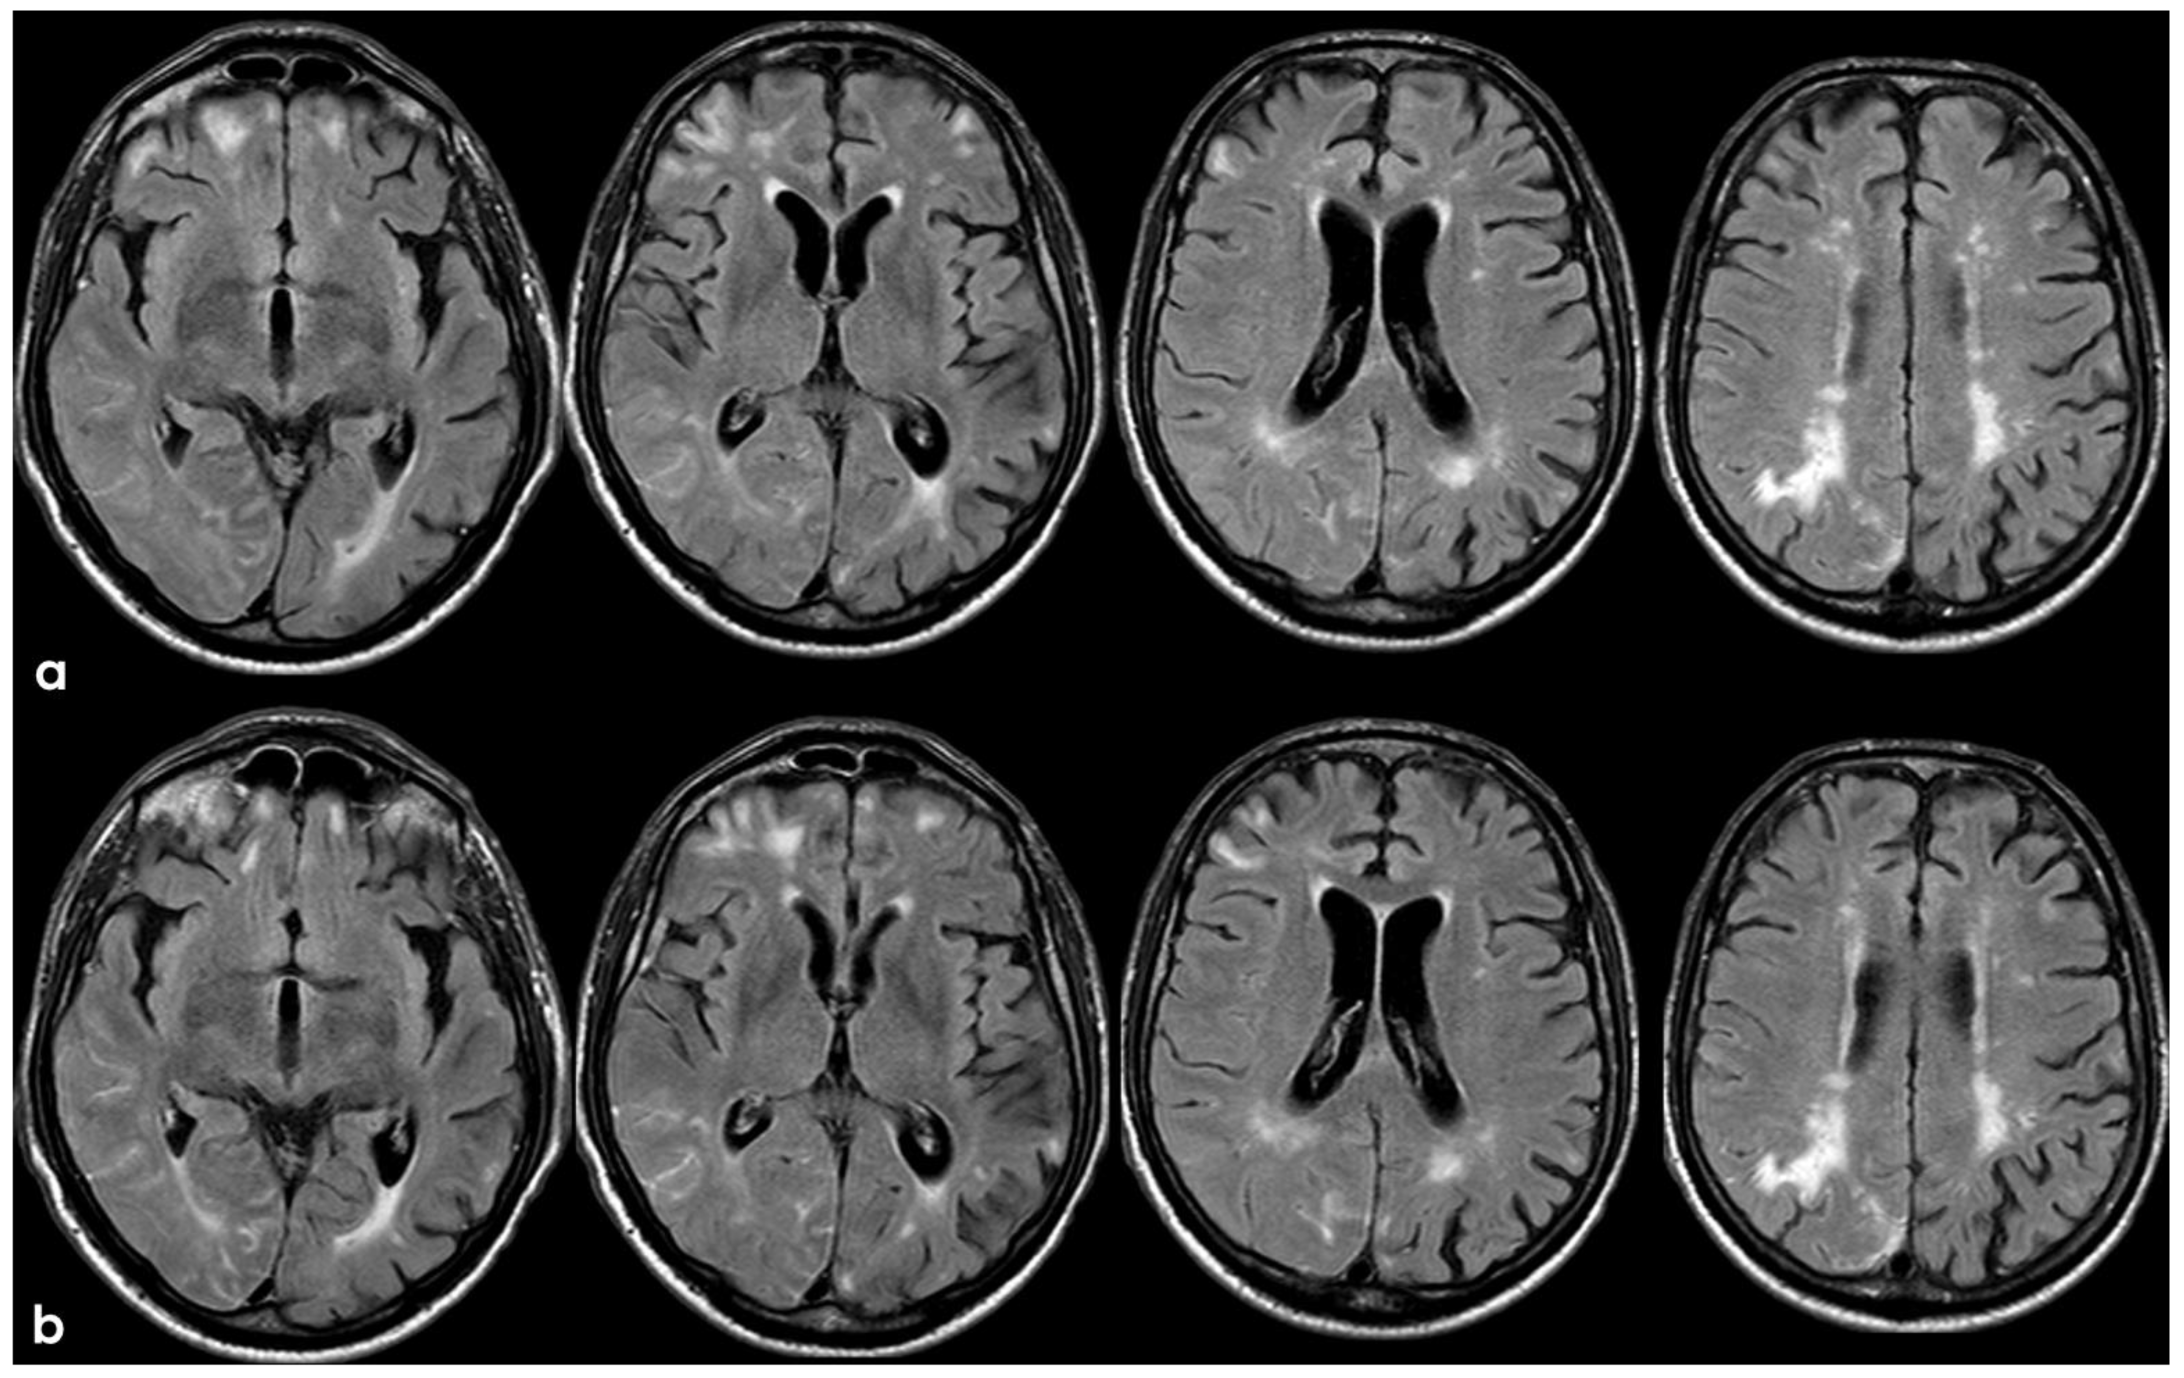

2. December 2013: Sulcal SAH and TFNEs

5. February 2017: First Recurrent CAA-Related Inflammation

6. December 2017: Recurrent SAH